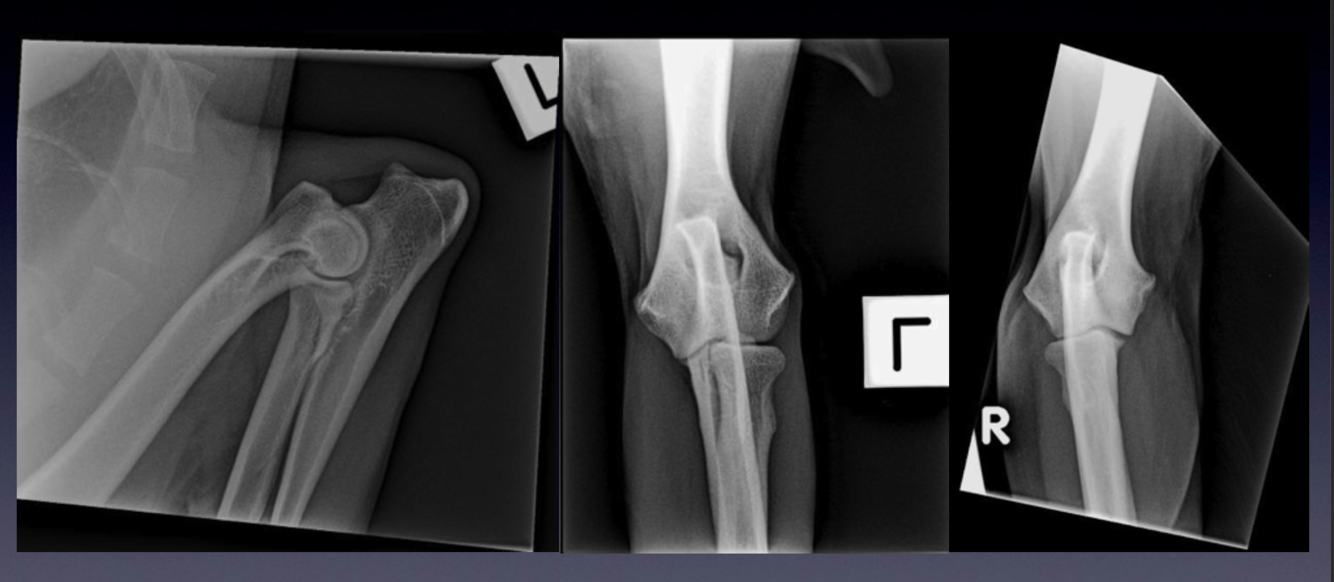

Case 6: Patient 237244

VIEW?

Compare these radiographs to the example of a normal elbow.

Please identify the following:

•

The irregular radiolucent line separating the anconeal process from the olecranon. This is

called an ununited anconeal process.

The following findings:

sclerosis at the base of the medial coronoid process of the ulna

irregular border to the medial coronoid process, as seen on the craniocaudal view

what problem do these findings indicate?

osteophyte formation along the proximal contour of the anconeal process

sclerosis of the ulna trochlear notch

what process is happening in this elbow joint?

Ununited anconeal process is one of the causes of elbow dysplasia. What are the other

potential causes of elbow dysplasia? What is the expected sequela of elbow dysplasia?

Flexed mediolateral and craniocaudal projections of the elbow of a dog.